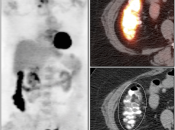

Presentation of Primary Cancer:

- Focal bowel uptake, usually with associated bowel wall thickening.

- If long-segment, think inflammation.

- If diffuse, usually normal physiologic uptake.

Metastases:

The most common sites of metastatic disease include the lymph nodes (regional & distant), liver, lung, peritoneal cavity, bones, brain and adrenal glands.